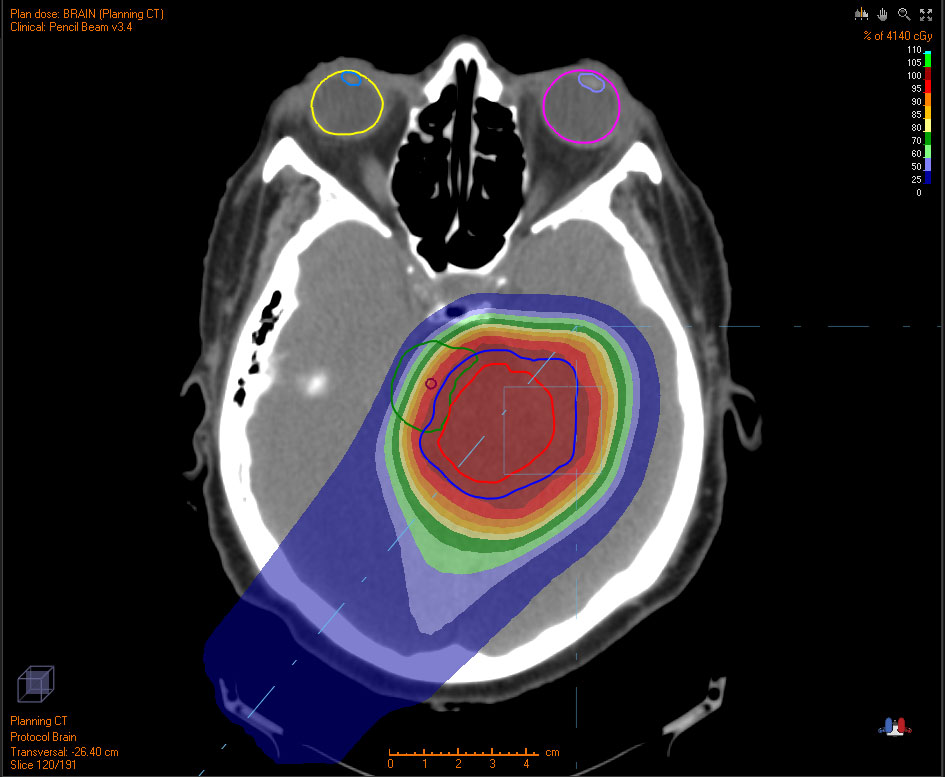

Below are examples of tumors treated with proton therapy and standard X-rays. In both cases, the tumor is treated with radiation. However, proton therapy delivers most of the radiation directly to the tumor, leaving much of the surrounding tissue unaffected. In contrast, standard X-ray radiation exposes a larger area of healthy tissue to radiation.

WITH PROTONS

Grey/white area indicates no radiation exposure.